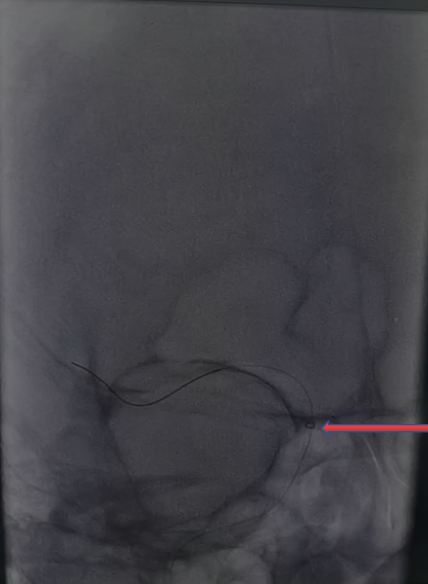

入院影像检查

急诊脑CT检查。

导丝怎么扩【载药时代 球扩天下】NOVA DES®颅内药物洗脱支架在颈内动脉颅内段重度狭窄的应用两例!滕州市中心医院&山西医科大学第二医院_https://www.jmylbn.com_新闻资讯_第3张

急诊DSA检查。

导丝怎么扩【载药时代 球扩天下】NOVA DES®颅内药物洗脱支架在颈内动脉颅内段重度狭窄的应用两例!滕州市中心医院&山西医科大学第二医院_https://www.jmylbn.com_新闻资讯_第4张

重要影像结论:左侧颈内动脉后交通段闭塞。